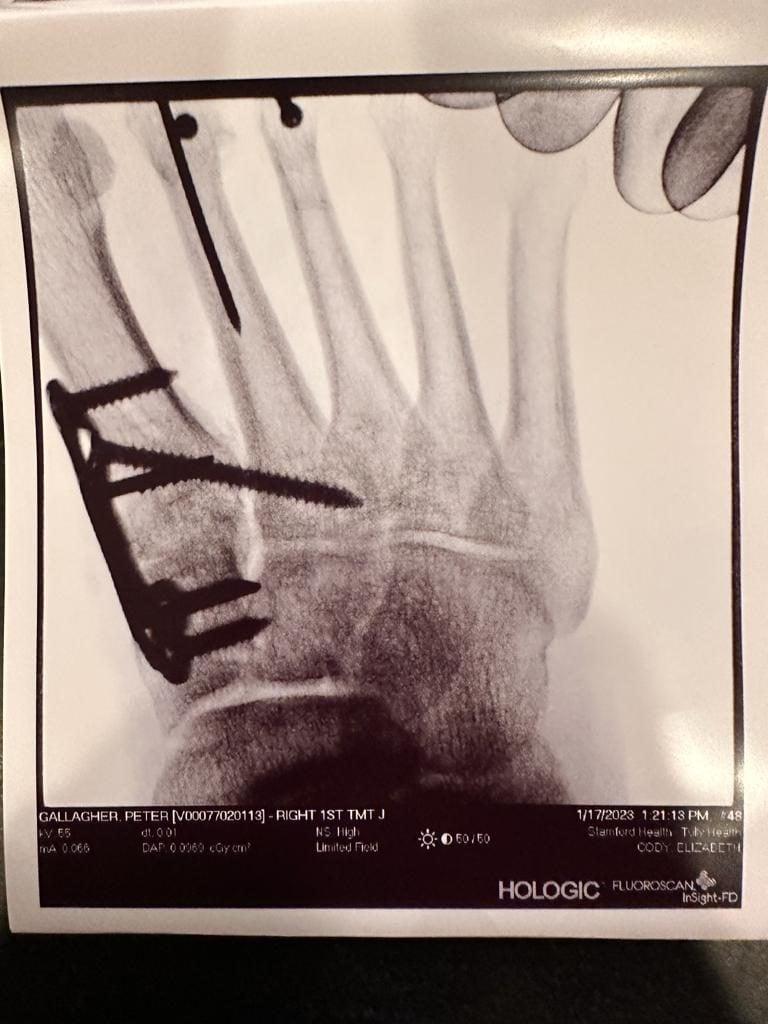

After more than 5 years of (right) foot pain, swelling, lots of anti-inflammatory drugs, etc., my GP referred me to HSS and Dr. Cody. At this stage my pain was intolerable. Unable to walk properly my quality of life had taken a nosedive. My podiatrist had recommended Yale and different foot specialist. I, of course, did my due diligence. HSS has an unrivaled world-class reputation for orthopedic surgery. Dr. Cody, too, has an outstanding reputation. The scene was set and I had my first consult. The exam was simple, diagnostic and explained at each stage. The x-ray similarly analyzed and explained. That resulted, in the now obvious to me, surgical procedure. It was a big surgery; 3 months of no weight-bearing, followed by physio. If I elected not to have surgery the consequences down the line were dire for my foot and my quality of life. This is all obvious good consulting process. But that is not the key thing. It was all calmly explained and all my questions were answered. I was reassured by the candid, open conversations with Dr. Cody.

The hospital was quick to schedule the procedure as my condition was deteriorating. The pre-op was perfect and reassuring. The post-op was also calmly explained to me. Dr. Cody also, importantly, briefed my wife, realizing that there are two people affected - the patient and the caregiver upon whom I would be reliant for at least 3 months. Immediately after the surgery I was released home. Dr. Cody called in the evening to inquire about my well-being. The follow up care, exams, x-rays, MRIs, etc., were all part of the process. The BUT is that all this followed a logical process, of where the healing was at, what I could do next to facilitate my recovery together with Dr. Cody, and her team being available should I have issues or questions. The post-op has been simple - I trusted the expert and her team, followed the instructions and am now one year free of pain, able to resume my normal life, including running! My quality of life is back to normal.